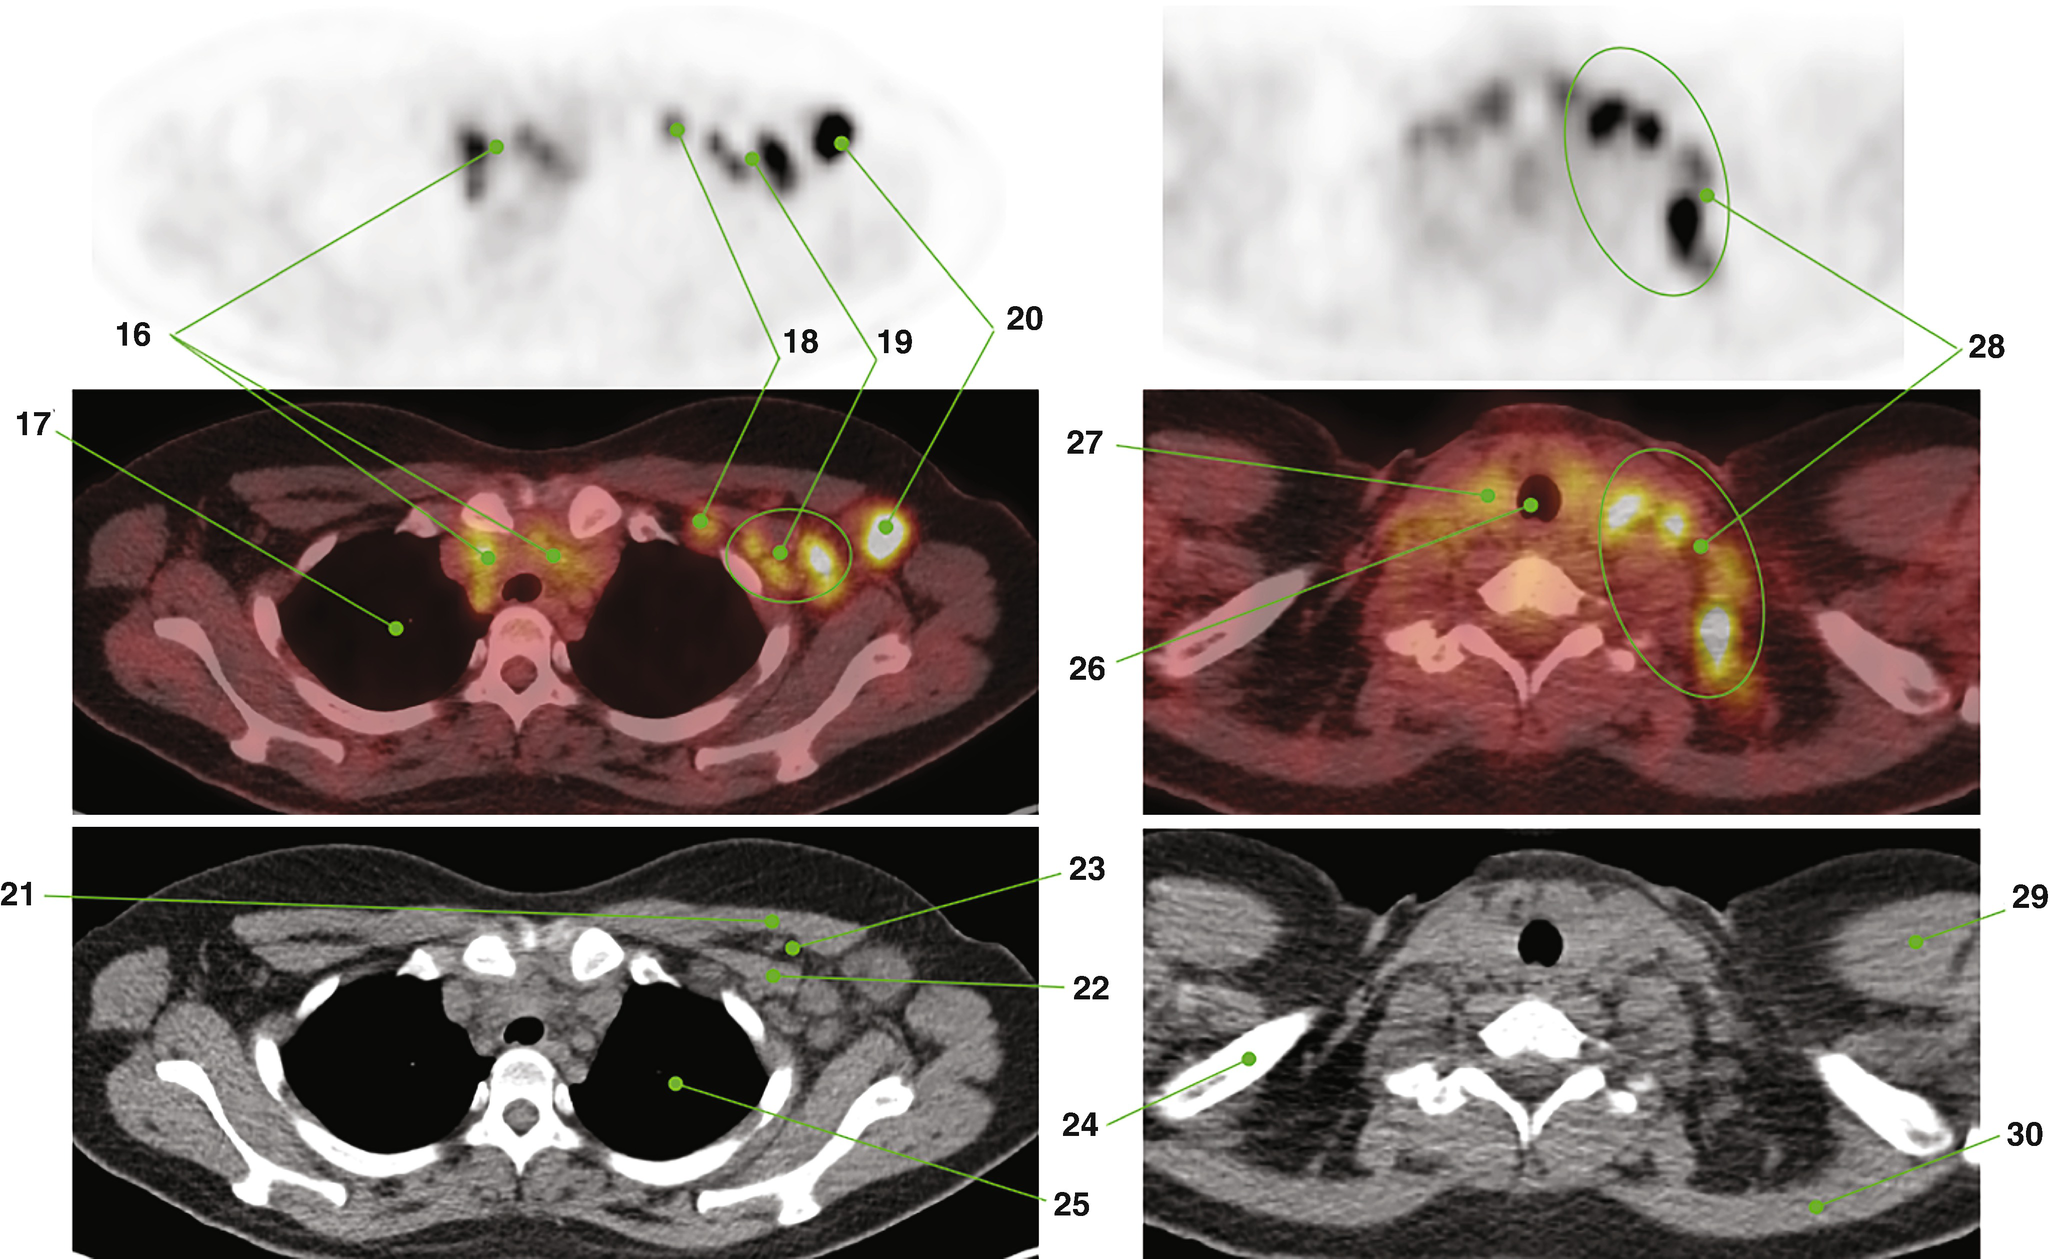

Facilitate learning with our scientific Pet/ct Lymphatic System gallery of hundreds of educational images. accurately representing photography, images, and pictures. perfect for research publications and studies. Browse our premium Pet/ct Lymphatic System gallery featuring professionally curated photographs. Suitable for various applications including web design, social media, personal projects, and digital content creation All Pet/ct Lymphatic System images are available in high resolution with professional-grade quality, optimized for both digital and print applications, and include comprehensive metadata for easy organization and usage. Explore the versatility of our Pet/ct Lymphatic System collection for various creative and professional projects. Multiple resolution options ensure optimal performance across different platforms and applications. Whether for commercial projects or personal use, our Pet/ct Lymphatic System collection delivers consistent excellence. Professional licensing options accommodate both commercial and educational usage requirements. Each image in our Pet/ct Lymphatic System gallery undergoes rigorous quality assessment before inclusion. Time-saving browsing features help users locate ideal Pet/ct Lymphatic System images quickly. Advanced search capabilities make finding the perfect Pet/ct Lymphatic System image effortless and efficient. Comprehensive tagging systems facilitate quick discovery of relevant Pet/ct Lymphatic System content. Instant download capabilities enable immediate access to chosen Pet/ct Lymphatic System images.